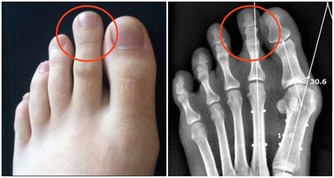

維生素B存在很多種,一般統稱為維生素B族,這可物質能夠讓人體的骨骼更加強壯,還能幫助促進人體新陳代謝。而當人體缺乏維生素B時,就可能引發多種疾病。

而缺乏維生素B6時,人的口唇、舌頭可能會有腫痛感,手指、腳趾還可能出現酥麻的刺痛感。